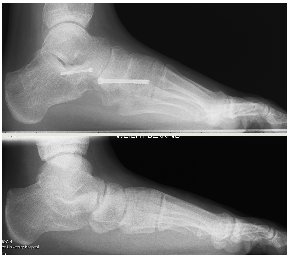

(Pre and post X-rays showing the line of the bone cuts and subsequently view post procedure with the calcaneum lengthened and rotated at the same time)

These X-rays show the foot from the side with initially a loss of arch height and a midfoot sag, in a young adult. Post procedure the lateral column has been lengthened using an Evans procedure with a navicular cuneiform fusion.

This has now been successfully realigned.